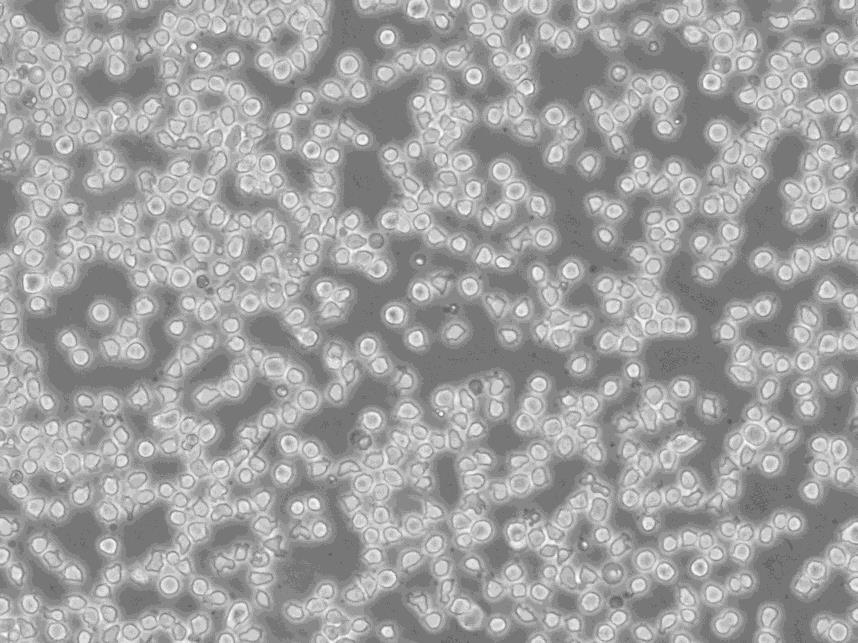

ZR-75-30 cells人乳腺癌细胞系

生长特性:贴壁生长

背景信息:源自一位47岁女性黑人更年期侵入性导管癌患者的腹水。

形态特性:上皮细胞样